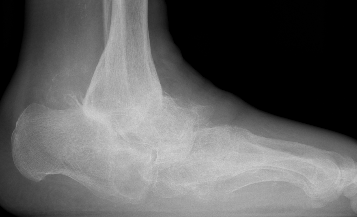

Xray

Midfoot collapse

Midfoot collapse and rocker bottom foot with small ulcer

Midfoot collapse with subluxation of midtarsal joints

Hindfoot collapse with ulcer